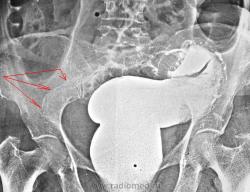

Пытались уточнить природу непроходимости. В ургентном порядке ирригоскопия.

Инвагинация????!!!!!! Или я ошибаюсь?

Опухоль ректосигмойдного отдела, раковый канал.

Для ракового канала слишком ровные контры, слишком симметрично, слишком длинно...все таки - инвагинация.

Чекто видно дефект напонения. Экзофитная опухоль.

Было дано заключение о наличии стенозирующей опухоли в сигме, что и подтвердилось на операции.

Анатолий Владимирович!

А, что это за штуковина в тазовой кости, помеченная красными стрелками?

Если проследить правый контур образования - видно что он уходит ниже кости..., вероятно это контур раздутой сигмы проксимальнее сужения. У пациентки классика системного остеопороза.

По мне так это просто пестрят костные балки, ну и конечно остеопроз. Таз женский